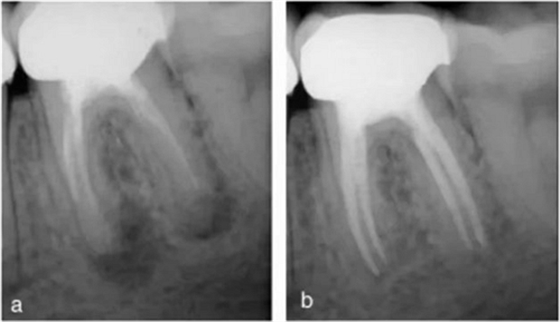

在歐洲人中,下頜第一磨牙的遠(yuǎn)中根大約 70%為單根管。15%為雙根管融合為單根管,5%為兩個(gè)獨(dú)立的根管,8% 為單根管分為雙根管,2%為單根管分為雙根管并再次于根尖1/3融合為單根管(8)(圖12a-b)。

在一些文獻(xiàn)中也有遠(yuǎn)中牙根三根管的報(bào)道。總體來說,病例中大約 30%的遠(yuǎn)中牙根為兩個(gè)或兩個(gè)以上根管。下頜磨牙的開髓洞型預(yù)備應(yīng)利于定位尋找第二個(gè)遠(yuǎn)中根管口。需要仔細(xì)檢查根管口的對(duì)稱性、形狀、位置及髓室底發(fā)育融合溝;如果只發(fā)現(xiàn)了狹窄的圓的遠(yuǎn)中根管口,需要懷疑是否存在另一個(gè)根管口。